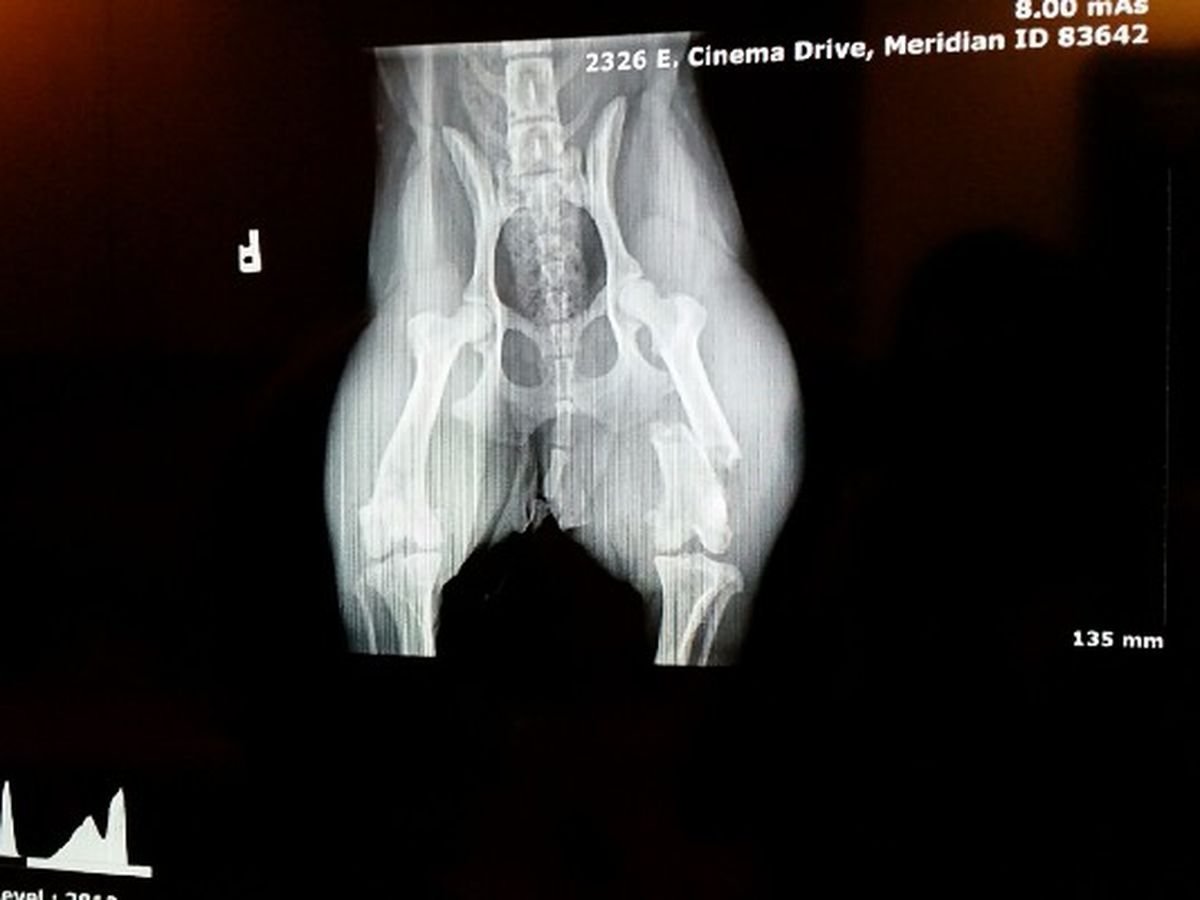

My sweet little girl Sadie escaped out of our backyard earlier this morning. Unfortunately, someone picked her up and made the decision to toss her small body off of a freeway overpass. Somehow, she survived with only a broken leg but the fracture is bad enough that it will require surgery. My sweet girl is only a little over a year old and has a lot of life left to live. The surgery is simple and the vet assures us she will make a full recovery.

The surgery itself is going to cost three thousands dollars. This covers the xrays, the pain medication, the surgery, and all of the follow ups. We just don't have the kind of funds required to pay for her surgery. Without this surgery, I would have to put my Sadie to sleep. It breaks my heart to think of that possibility and I'm asking for anyone who could help us out at all. Anything would be appreciated. We don't have a lot of time to try and raise the money for her surgery. If you could share this story and pass it along we would be truly blessed.